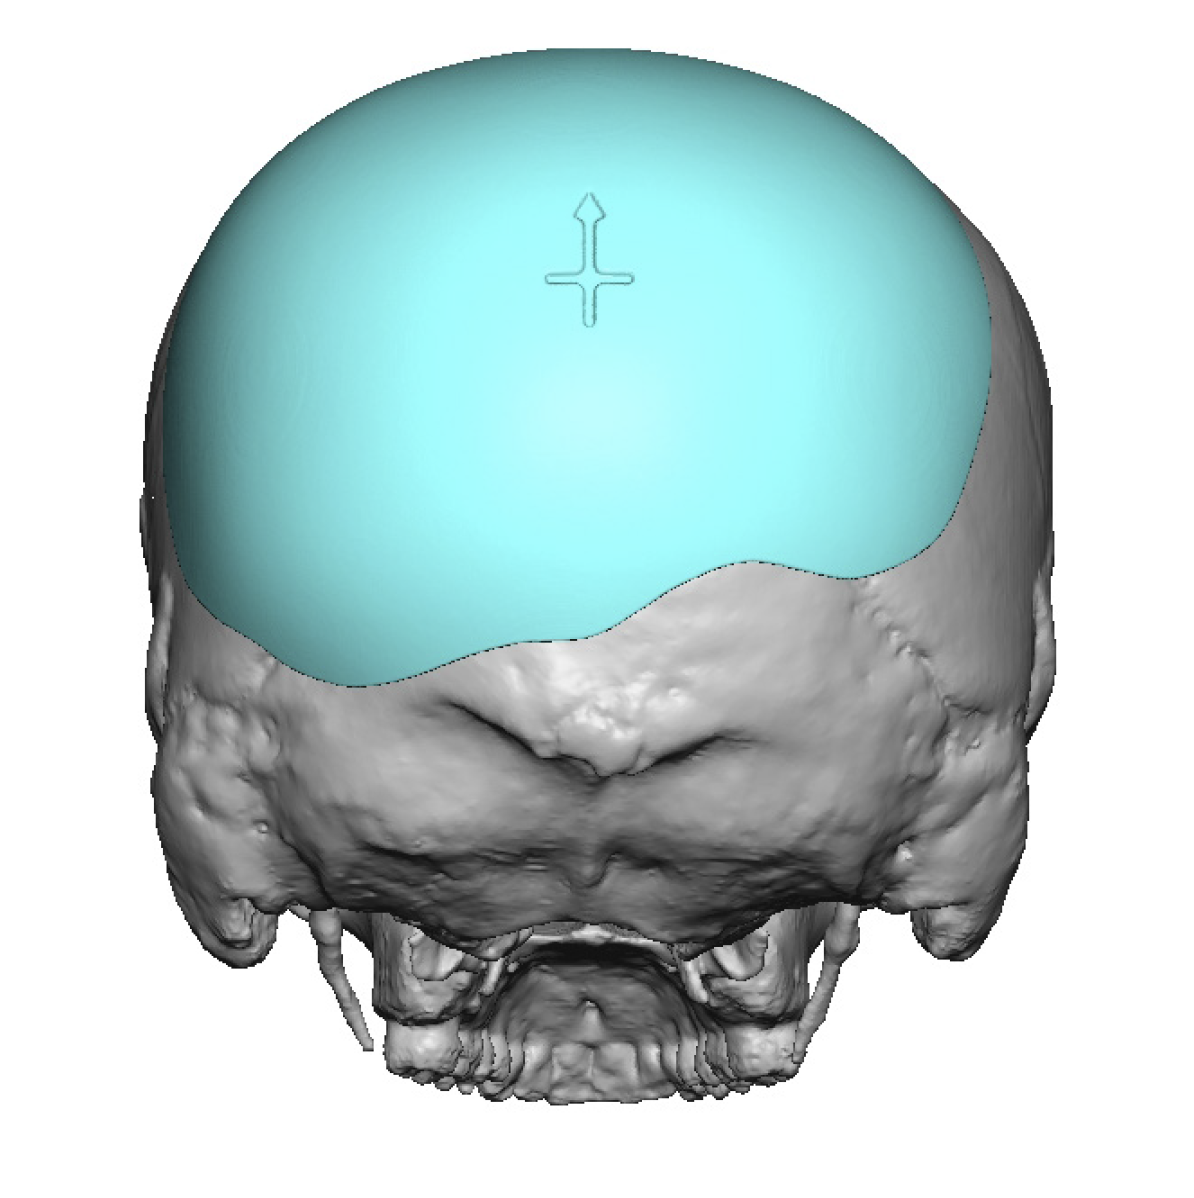

Patient 12

Desire to make her small head taller and wider.

Two stage skull augmentation using a first stage scalp expansion and a second stage custom skull implant for increased head height and shape.

Desire to make her small head taller and wider.

Two stage skull augmentation using a first stage scalp expansion and a second stage custom skull implant for increased head height and shape.